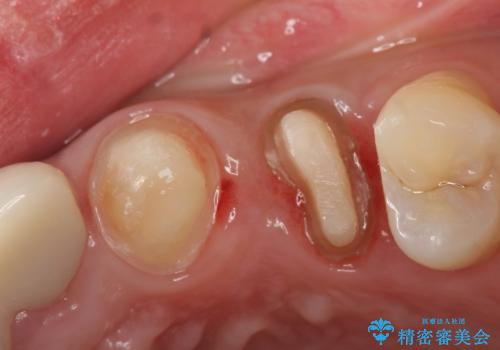

- 左上3、4番の見た目が気になるためセラミックにしたいといらっしゃった方の症例です。

左上4の補綴物を除去したところ縁下歯質だったため、歯牙の挺出を提案し行いました。

挺出終了後は歯肉切除および骨外科により歯周組織を整え、オールセラミッククラウンによる補綴を行いました。